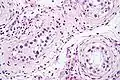

- ITGCN. H&E stain.

GCNIS is not palpable, and not visible on macroscopic examination of testicular tissue. Microscopic examination of affected testicular tissue most commonly shows germ cells with enlarged hyperchromatic nuclei with prominent nucleoli and clear cytoplasm. These cells are typically arranged along the basement membrane of the tubule, and mitotic figures are frequently seen. The sertoli cells are pushed toward the lumen by the neoplastic germ cells, and spermatogenesis is almost always absent in the affected tubules. Pagetoid spread of GCNIS into the rete testis is common. Immunostaining with placental alkaline phosphatase (PLAP) highlights GCNIS cell membranes in 95 percent of cases. OCT3/4 is a sensitive and specific nuclear stain of GCNIS.[3]